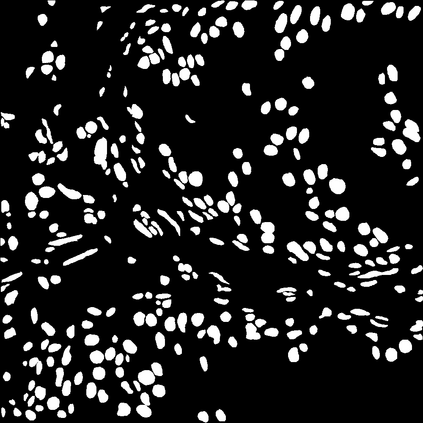

Due to the limitation of available labeled data, medical image segmentation is a challenging task for deep learning. Traditional data augmentation techniques have been shown to improve segmentation network performances by optimizing the usage of few training examples. However, current augmentation approaches for segmentation do not tackle the strong texture bias of convolutional neural networks, observed in several studies. This work shows on the MoNuSeg dataset that style augmentation, which is already used in classification tasks, helps reducing texture over-fitting and improves segmentation performance.